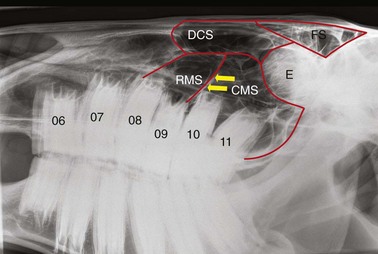

The apices of some equine maxillary cheek teeth are positioned within the paranasal sinuses, and knowledge of this anatomic relationship is important in order to detect changes due to periapical infections (Fig. 13.31). Although there is some individual variation, generally the apices and reserve crown of the 06s and 07s and rostral aspect of the 08s (Fig. 13.30) lie within the radio-opaque, rostral aspect of the maxillary bone, and therefore, a slightly higher exposure is required to image these optimally. The caudal aspect of the maxillary 08s and all of the 09s are generally positioned within the rostral maxillary sinus, and the maxillary 10s and 11s lie within the caudal maxillary sinus (Fig. 13.31).

image

Fig. 13.31 Anatomy of the paranasal sinuses as viewed in a lateral radiograph. RMS, rostral maxillary sinus; CMS, caudal maxillary sinus; DCS, dorsal conchal sinus; FS, frontal sinus; E, ethmoturbinates; arrows, rostrolateral portion of the maxillary sinus septum. The 06 and 07 are positioned rostral to the paranasal sinuses.

The rostral and caudal maxillary sinuses are usually completely separated by a thin obliquely oriented bony septum which on lateral or lateral-oblique radiographs originates adjacent to the caudal aspect of the upper 09s, and courses from rostrolateral to caudomedial. Although the maxillary sinus septum is not always radiographically distinguishable from other intrasinus septae, its most lateral aspect is often represented by a linear radiopacity,11 extending dorsocaudally from the caudal aspect of the upper 09s (Fig 13.31). The position of the maxillary sinus septae may vary between right and left sides. The infra-orbital canals are radiographically apparent on lateral and lateral-oblique radiographs, lying directly dorsal to the apices of the caudal cheek teeth in young horses.